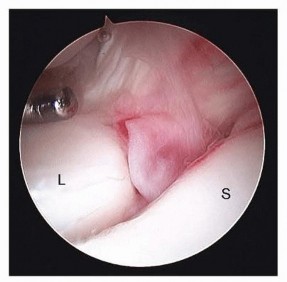

It is useful to have a systematic approach to viewing the wrist.The structures that should be visualized as a part of a standard examination include the radius articular surface; the proximal scaphoid, lunate, and triquetrum; the SLIL and lunotriquetral interosseous ligament (LTIL), both palmar and dorsal; the radioscaphocapitate ligament; the long radiolunate ligament; the radioscapholunate ligament; the ulnolunate ligament; the ulnotriquetral ligament; the articular disc; and the radial and peripheral TFCC attachments.Many procedures can be done without fluid, which minimizes the amount of swelling and fluid extravasation. Intermittentirrigation with a 10-mL syringe attached to the inflow portal of the arthroscope followed by suction with the full radius resector can help clear the field.The volar radial portal is used in patients with radial-sided and dorsal wrist pain to visualize the palmar SLIL and the DRCL.In patients with ulnar-sided wrist pain, the volar ulnar portal is used to assess the palmar LTIL and dorsal radioulnar ligament, the region of the ECU subsheath, and the radial TFCC attachment.The scope is then inserted in the 3-4 portal followed by various combinations of the 4-5 portal and 6R portal. The 6U portal is mostly used for outflow, but it may be used for instrumentation when débriding palmar LTIL tears.Midcarpal arthroscopy is then performed to probe the SLIL and LTIL joint spaces for instability, the capitohamate interosseous ligament, and to look for chondral lesions on the proximal capitate and hamate and loose bodies.The special-use portals such as the dorsal and volar DRUJ portals and the 1-2 portal are used as needed.